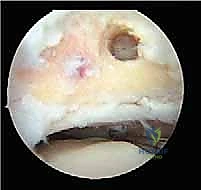

5. آفات الغضروف العظمي (Osteochondral Lesions - OCL)

هي إصابات بؤرية تصيب الغضروف المفصلي والعظم الذي تحته، غالباً في قبة عظم الكاحل (Talar Dome). إذا كانت هذه الآفات تقع في الجزء الخلفي من المفصل، فإن الوصول إليها وعلاجها يكون مثالياً عبر المنظار الخلفي.

* معالجة الغضاريف: تنظيف الآفات الغضروفية وتحفيز النخاع العظمي (Microfracture) لتكوين غضروف ليفي جديد.